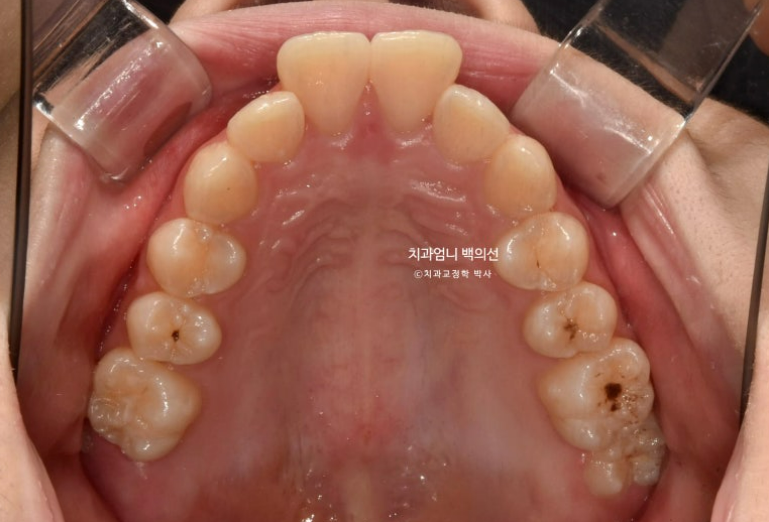

25.06

중심선은 잘 맞습니다.

유난히 커보이던 앞니는 돌출이 해소되고 가지런해지면서 누명을 벗었습니다.

교합은 좋습니다.

간혹 작은어금니 발치교정은 4개를 빼야 교합이 맞지 않나에 대한 질문을 듣는데 위에만 돌출인 경우 위에만 2개 빼는 교정도 좋은교합으로 마무리 되는 교정이랍니다.

치근흡수는 없고 치근평행도는 좋습니다.